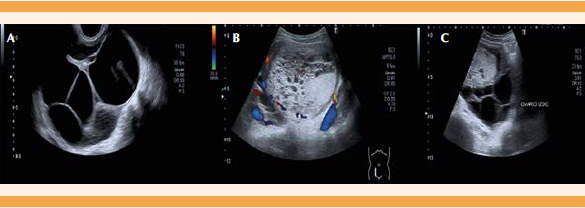

A su llegada al Hospital de la Mujer, en la exploración evidenció abdomen globuloso, con tumoración pélvica que abarcaba todo el hipogastrio, incluso hasta la zona umbilical. En la ecografía transabdominal y transrrectal se visualizaron ambos ovarios aumentados de tamaño, a expensas de múltiples formaciones quísticas y útero hipertrófico dependiente de una formación heterogénea que parecía tener origen intracavitario. Se informó a los familiares y a la paciente la necesidad de un estudio pormenorizado y se ingresó para completarlo. Se le practicaron estudios de ecografía Doppler de alta resolución, hemograma, bioquímica y coagulación. De esta última, el único dato destacable fue la anemia moderada, con hemoglobina (Hb) de 9.4 g/dL. La ecografía-Doppler (Figura 1) describió: útero desplazado por formación hiperecogénica de bordes regulares, de aspecto sólido, con áreas anecoicas en su interior, de 114 mm de diámetro longitudinal por 84 mm de diámetro transversal, que comprimía la pared miometrial, adelgazando su grosor hasta 8 mm. Al Doppler color mostró muy escasa vascularización interna. El ovario derecho estaba en el fondo de saco de Douglas, de 90 x 75 mm, con múltiples formaciones anecoicas, similar al ovario izquierdo, ambos compatibles con quistes tecaluteínicos.

Figura 1 Ecografía abdominal: A. Ovario derecho aumentado de tamaño, con múltiples formaciones anecoicas (quistes tecaluteínicos). B. Masa uterina intracavitaria, de aspecto sólido, con áreas anecoicas que comprimen la pared miometrial y adelgazan su grosor, incluso 8 mm. Al aplicar Doppler color se observa escasa vascularización. C. Ovario izquierdo aumentado de tamaño, con quistes tecaluteínicos.